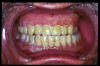

CM Caries, patología periodontal, desgaste.